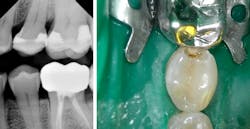

As previously mentioned, I routinely do Canary scans of rotating quadrants, focusing on nonrestored occlusal and interproximal surfaces. At this particular appointment it was the lower-left quadrant’s turn to be scanned. Teeth Nos. 18 and 19 are restored, so Nos. 20, 21, and 22 were scanned occlusally and interproximally. No. 20 clinically appeared to be normal, and the bitewing was unremarkable.

The distal-interproximal Canary Number, however, was 37, so I knew there was active caries. After the distal was opened, caries was discovered and conservatively removed, and the tooth was restored.